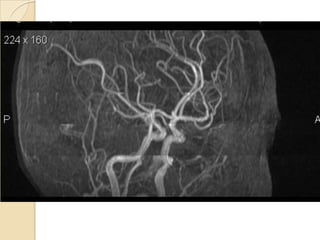

Arteries of the brain (cranial view) - MRA

1. Anterior cerebral artery

2. Anterior communicating artery

3. Basilar artery

4. branches (in insula) of middle

cerebral artery

5. Cavernous portion of internal

carotid artery

6. Cervical portion of internal carotid

artery

7. Genu of middle cerebral artery

8. Intracranial (supraclinoid) internal

9. Middle cerebral artery

10. Ophthalmic artery

11. Petrous portion of internal carotid

12. Posterior cerebral artery

13. Posterior cerebral artery in ambient

cistern

14. posterior cerebral artery in

interpeduncular cistern

15. Posterior communicating artery

16. Posterior inf cerebellar artery.

17. Quadrigeminal portion of posterior

18. Superior cerebellar artery

19. Vertebral artery